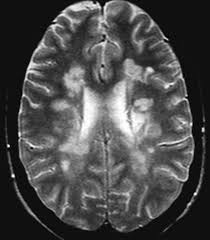

Los avances en la esclerosis múltiple

En los últimos años se han producido grandes avances en la enfermedad de la esclerosis múltiple, tanto en el conocimiento de la enfermedad, como en los diagnósticos y las terapias que se pueden aplicar.

A pesar de estos avances, aún quedan muchas lagunas y campos de mejora. Uno de los desafíos es conseguir terapias personalizadas para cada uno de los pacientes que sufren esta enfermedad. Se habla de desafío debido a que la esclerosis múltiple destruye la sustancia que recubre los nervios, llamada mielina, y por lo tanto puede afectar a diferentes partes del cuerpo y tiene un cuadro clínico muy amplio. Esto se complica si tenemos en cuenta que la esclerosis reporta un fenómeno inflamatorio y otro degenerativo.